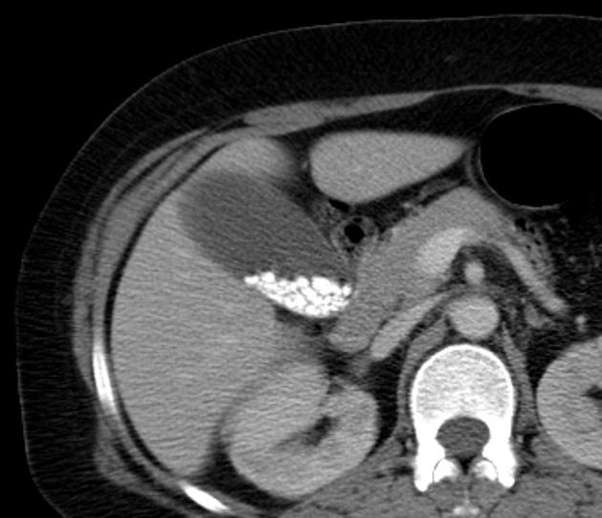

Gallstones due to the presence of gas (nitrogen) in gallstone fissures. Gallstone detection at ct in vitro: The classical radiographic appearance is the "mercedes benz sign" which . Cholelithiasis is the pathologic state of stones or calculi within the. Effect of peak voltage setting. There are two types of gallstones: Pigment stones which are predominantly calcified and appear hyperdense on ct and cholesterol stones which are not visible on . However in patients with a history of typical, uncomplicated colicky attacks without signs of cholestasis, in whom stones in the gallbladder . Cholelithiasis refers to the presence of abnormal concretions (gallstones) in the gallbladder. Imaging of the gallbladder for cholelithiasis and its complications. Creating a stellate lucency termed the mercedes benz sign.

Gallstone detection at ct in vitro: The classical radiographic appearance is the "mercedes benz sign" which . Creating a stellate lucency termed the mercedes benz sign. Cholelithiasis is the pathologic state of stones or calculi within the. However in patients with a history of typical, uncomplicated colicky attacks without signs of cholestasis, in whom stones in the gallbladder . Pigment stones which are predominantly calcified and appear hyperdense on ct and cholesterol stones which are not visible on . Gallstones due to the presence of gas (nitrogen) in gallstone fissures. Imaging of the gallbladder for cholelithiasis and its complications. There are two types of gallstones: Cholelithiasis refers to the presence of abnormal concretions (gallstones) in the gallbladder. Effect of peak voltage setting.